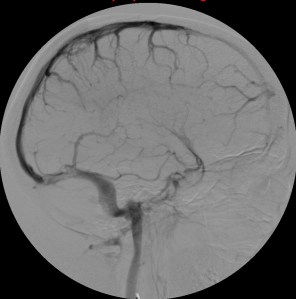

Se procede a la intervención de la paciente con realización de Arteriografía.

Venografía RM:

El protocolo recomendable ante la sospecha de una TVC es realizar, además de secuencias potenciadas en T1 y T2 en al menos 2 planos, secuencias de venografía-RM con técnica Contraste de Fase para descartar ausencia de flujo en los senos venosos principales. Si persiste la duda diagnóstica se puede administrar contraste para demostrar el signo del delta o bien, finalmente, realizar otras secuencias de venografía, como 2D-TOF (tiempo de vuelo) o T1 3D con contraste. Veremos: Ausencia señal de flujo en seno y formación anómala de circulación colateral. . Seno irregular (recanalización). Flujo prominente en venas medulares profundas. Gran detalle anatómico.